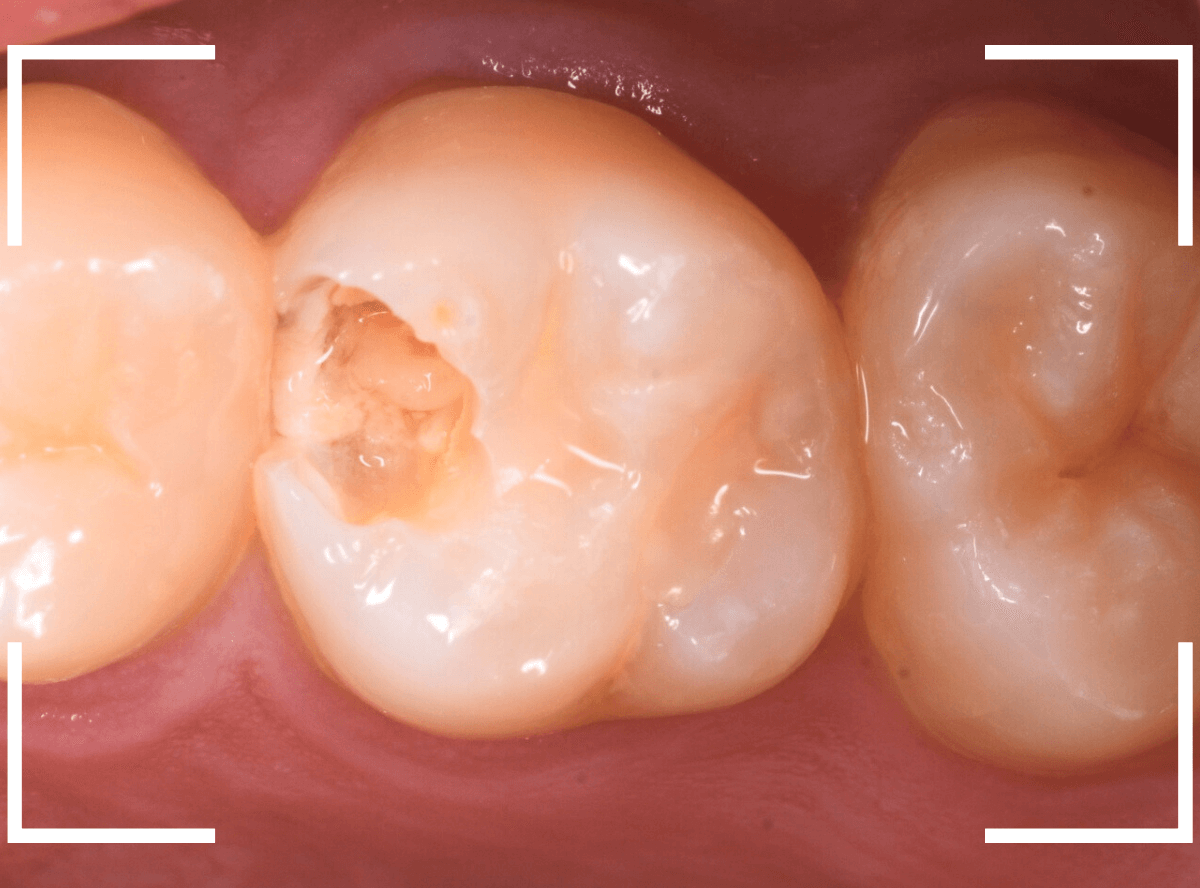

上の奥歯が痛むという訴えで来院された患者さんです。

一番奥の歯(左)が虫歯になっているのが一目でわかります。

虫歯も深そうです。

レントゲン写真で確認します。

赤い線が虫歯、青い線が歯の神経です。

歯の神経までは少し距離がありそうですが、深い虫歯であるのはわかります。

となりのつめもの(レジン)の下も虫歯になっているのがわかります。

治療を開始します。

赤く染まっている部分が虫歯です。

思った通り、かなり深く進行していますね。

奥歯の虫歯が全部除去できましたので、手前の歯の虫歯も治療します。

全ての虫歯を除去しました。

レントゲンから予測した通り、かなり広範な虫歯でした。

お薬をつめて、しばらく症状がないか経過観察後、つめものを作る治療に移ります。